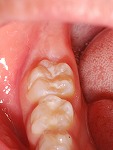

~シーラント~

小児歯科

術前

術後